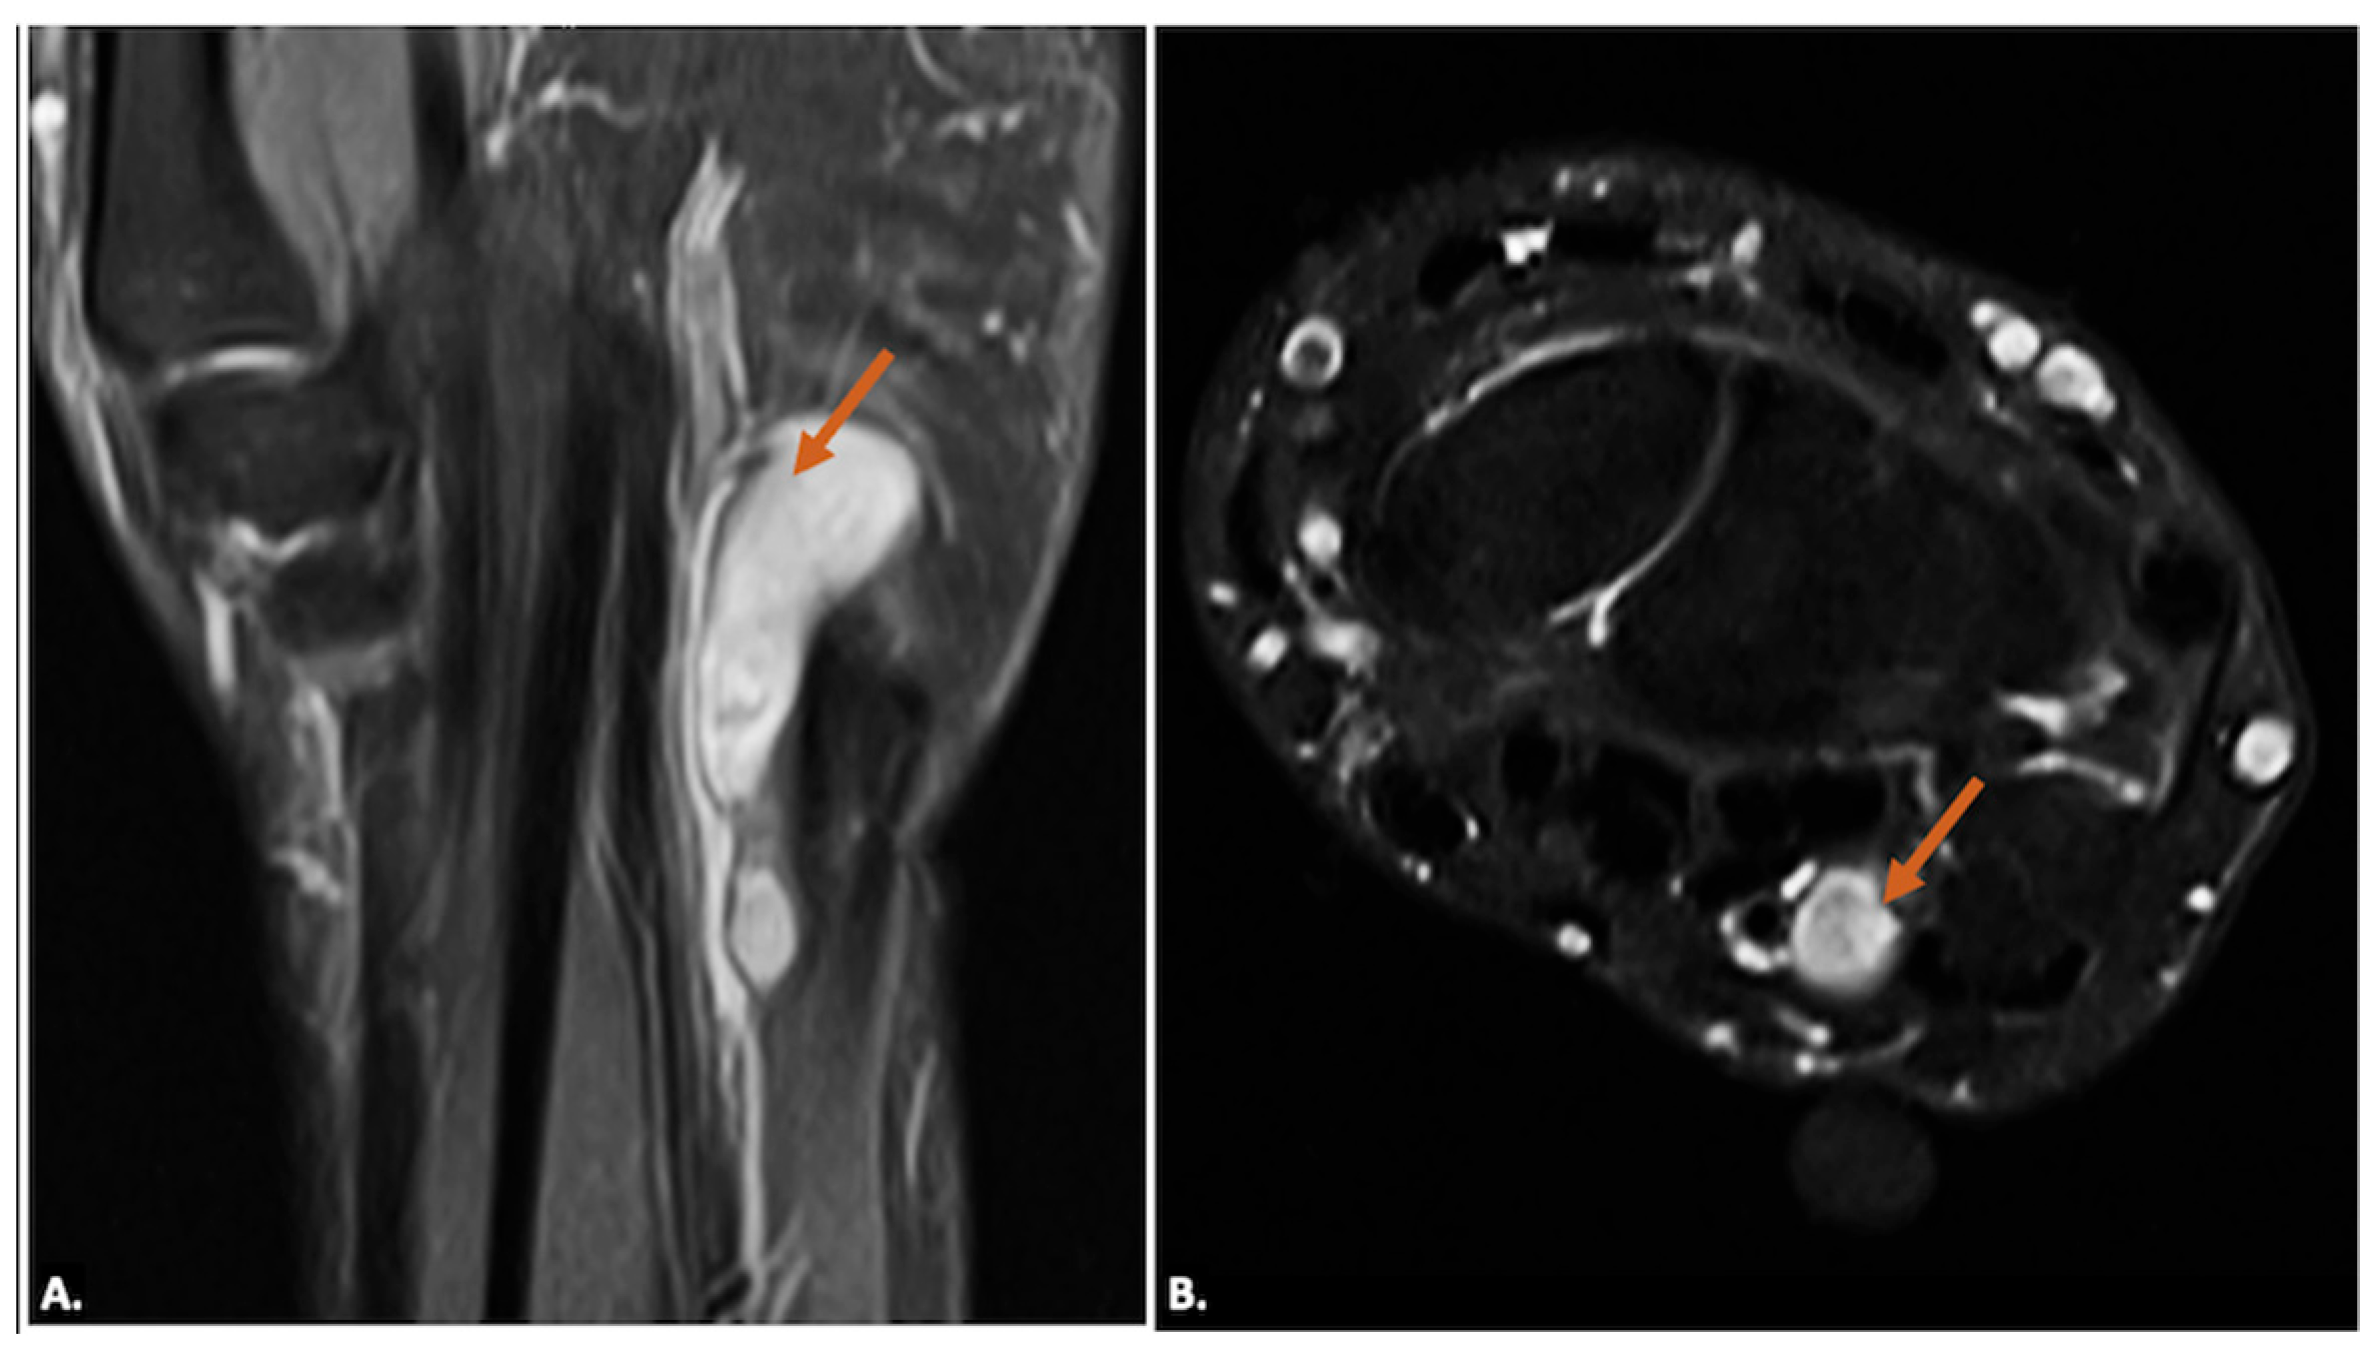

4.2. Hypothenar Hammer Syndrome (HHS)

| Traumatic Injuries (Hook of Hamate Fracture, HHS, Nerve Laceration, Stump Neuroma) | Nerve laceration: Hypoechoic discontinuity with possible neuroma formation (bulbous enlargement). Fractures: May be occult on standard radiograph and on ultrasound. HHS: Vascular abnormalities on Doppler. | Fractures: Best seen on CT/MRI if radiographs are inconclusive. Neuroma: T2 hyperintensity with possible nerve thickening and discontinuity. HHS: Aneurysm/thrombosis findings. |